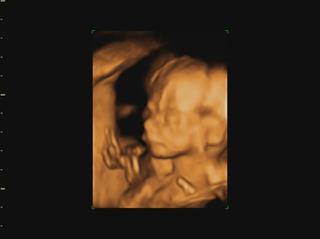

Ahojte kočky, konečne mam trošku času tak si idem spätne prečítať čo ste napísali... a pochváliť vám krásne brušinká 😀 medzi tým Vám pridám moje brušo a našu Izzy neposednú. Máme aj video, ale to som dala len FB, lebo tu sa pridať nedá. Fotky aj video je trochu rozmazané, lebo mala v kuse so sebou narabala... a ano pipik nam nedorastol... 😀